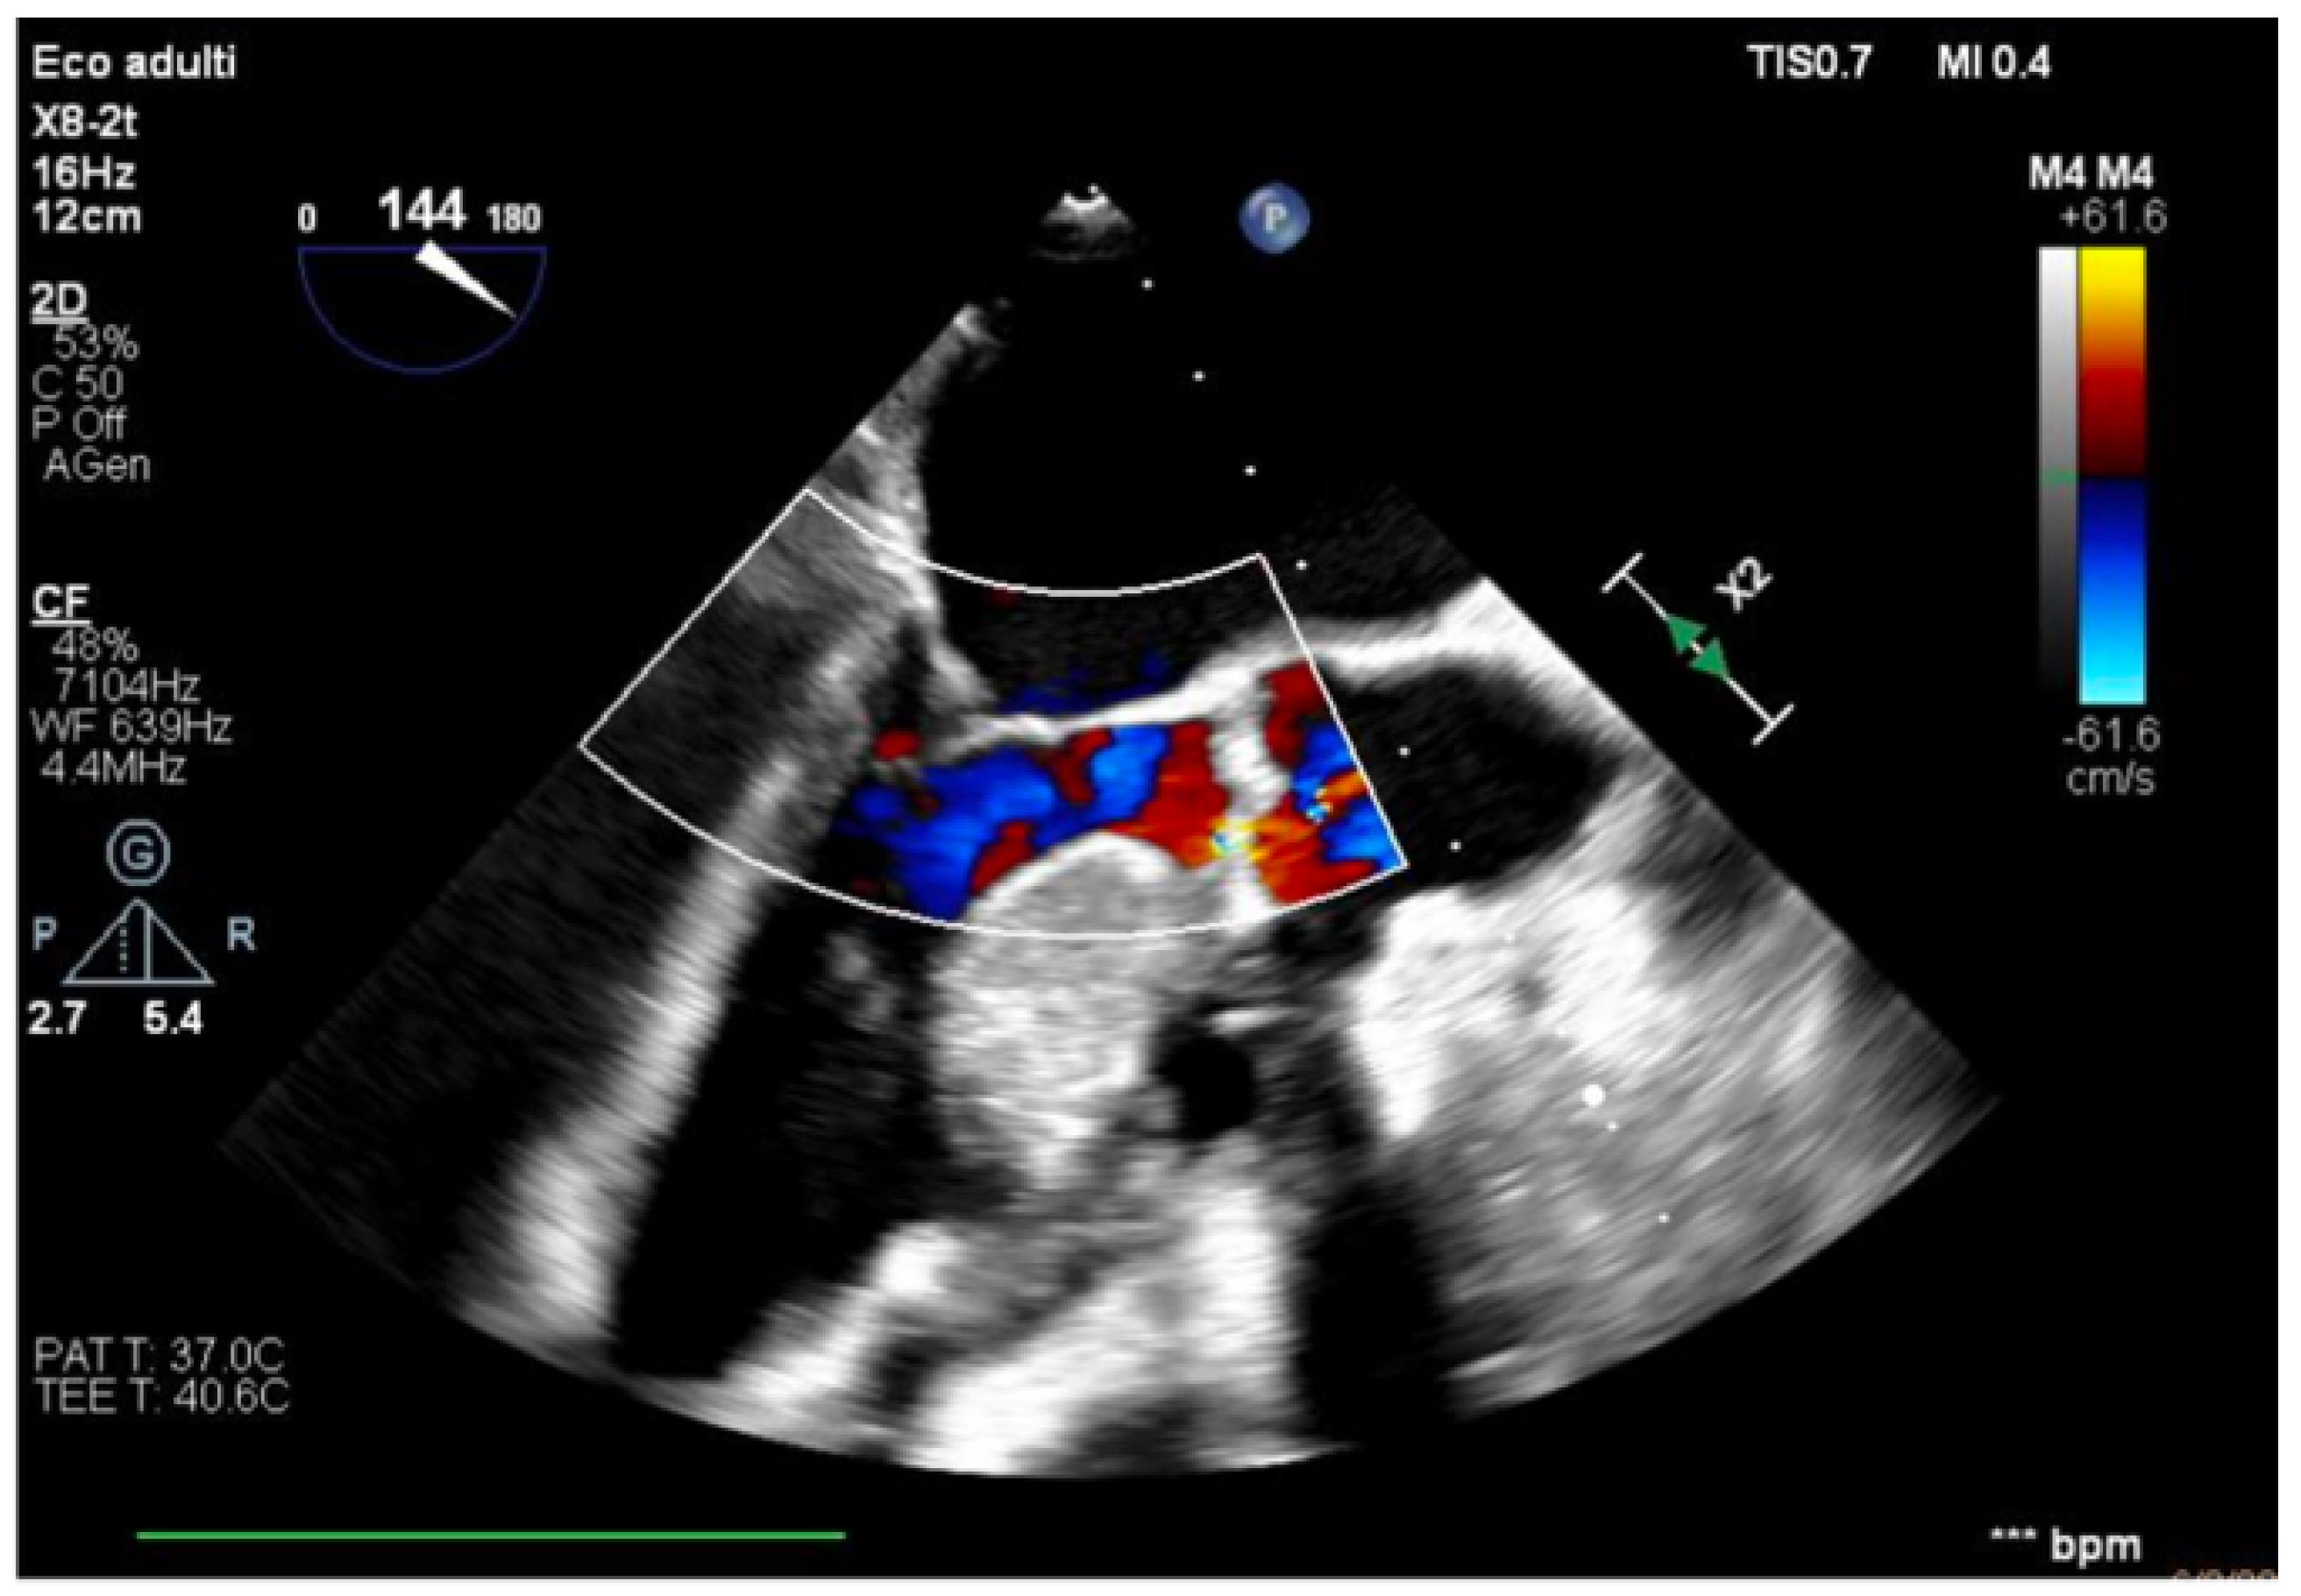

We describe a case of a 75-year-old woman affected by a post-myocardial-infarction ventricular septal defect (VSD) and a left-ventricle (LV) apical aneurysm. The patient underwent surgery for VSD closure and aneurysm exclusion. The patient had a STEMI (ST-elevation myocardial infarction), with evidence of occlusion of the anterior interventricular artery, for which thrombus aspiration and stenting of the left coronary artery and proximal anterior interventricular artery was performed. Then, she developed cardiogenic shock with pulmonary edema and thus required the support of an IABP (intra-aortic balloon pump) of C-PAP and levosimendan in continuous infusion for 24 h. Seven days after the event, a large post-infarct VSD at the apical level with a left–right shunt occurred. She was therefore transported from the spoke center to our hospital and underwent surgical treatment, namely, post-infarct VSD closure and exclusion of a left ventricular aneurysm. The intra-operative transesophageal echocardiography showed concentric LV remodeling, slight dilatation, LVEF 28% (Figure 1), and akinesia of the mid-apical segments in toto with aneurysmal evolution (Figure 2).

Figure 1. Mid-esophageal four-chamber view.